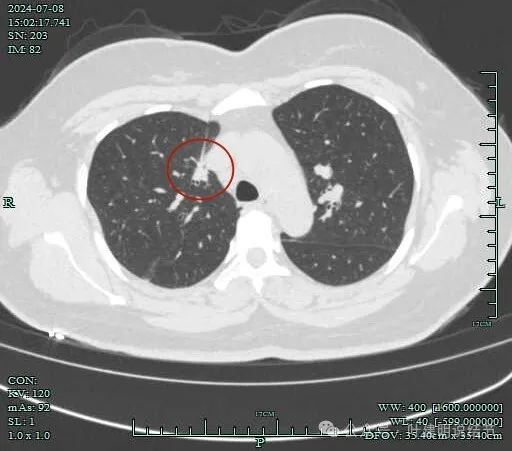

再看2024年7月份的影像:

肺窗上见与上腔静脉紧贴着,病灶边缘稍显模糊。

病灶边上不清爽。

病灶有毛刺与小棘突征,有邻近细支气管扩张,表面不平,膨胀性不明显。

毛刺征明显,灶边细支气管扩张。

病灶整体轮廓还是较为清楚的。

病灶边支气管可见。